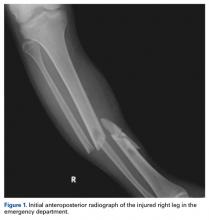

A 23-year-old unrestrained driver of a tow truck rear-ended another vehicle at high speed (~45 mph) and became trapped in the vehicle. Extrication time was prolonged. The driver was brought to the emergency department at a level I trauma center, where he was found to have an obvious closed deformity of the right lower leg but remained neurovascularly intact. Radiographs showed a highly comminuted fracture of the right tibial and fibular midshaft with more than 100% medial displacement of the distal fragment (Figure 1).